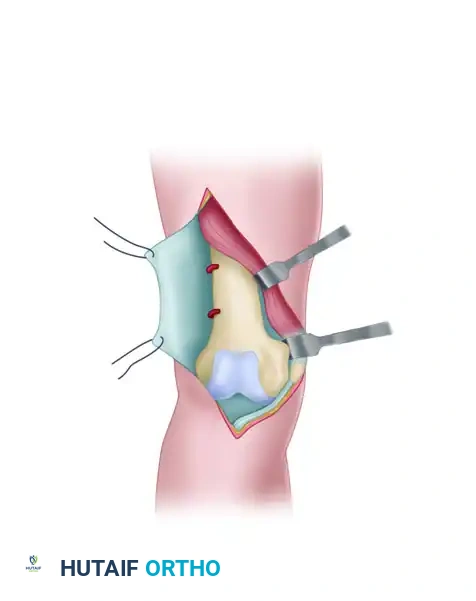

FIGURE 54-74 A: Swashbuckler technique. The fascia overlying the quadriceps is incised longitudinally and lifted laterally off the underlying muscle.

- Arthrotomy: Farther laterally, the fascia over the quadriceps becomes confluent with the iliotibial band. A lateral parapatellar arthrotomy is performed. Proximally, the arthrotomy incision is carefully developed between the vastus lateralis muscle and the lateral retinaculum of the knee.

FIGURE 54-74 B: Swashbuckler technique. The lateral parapatellar arthrotomy is performed, separating the vastus lateralis from the lateral retinaculum.

- Proximal Release and Eversion: Proximal release of the vastus lateralis fibers from the lateral intermuscular septum allows for further mobilization of the quadriceps mechanism. The patella is everted medially, exposing the entire distal femur.

FIGURE 54-74 C: Swashbuckler technique. Proximal release of the vastus lateralis fibers from the lateral intermuscular septum allows further mobilization. Perforating vessels are controlled with cautery, and the patella is medially everted.